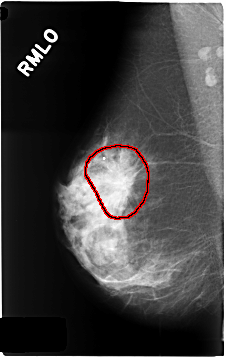

C_0339_1.RIGHT_MLO

RIGHT_MLO LINES 4640 PIXELS_PER_LINE 2928 BITS_PER_PIXEL 12 RESOLUTION 50 OVERLAY

FILE: C_0339_1.RIGHT_MLO.OVERLAY

TOTAL_ABNORMALITIES 1

ABNORMALITY 1

LESION_TYPE MASS SHAPE IRREGULAR MARGINS SPICULATED

ASSESSMENT 5

SUBTLETY 5

PATHOLOGY MALIGNANT

TOTAL_OUTLINES 1

BOUNDARY